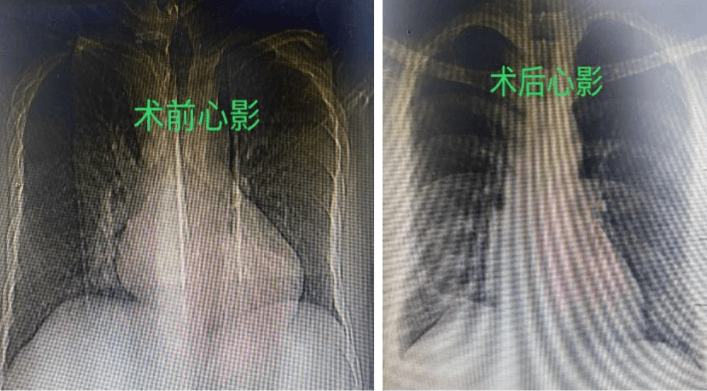

7月25日,在麻醉团队、体外循环等团队的保驾护航下,祝恒山主任带领的手术团队在张先生的右侧腋下切口了一个不到5厘米的小切口,开始为患者实施二尖瓣成形术和房间隔缺损修补术,不到3个小时,手术团队便顺利地为患者的心脏进行了“修补”,术后复查胸片及心脏超声效果满意。